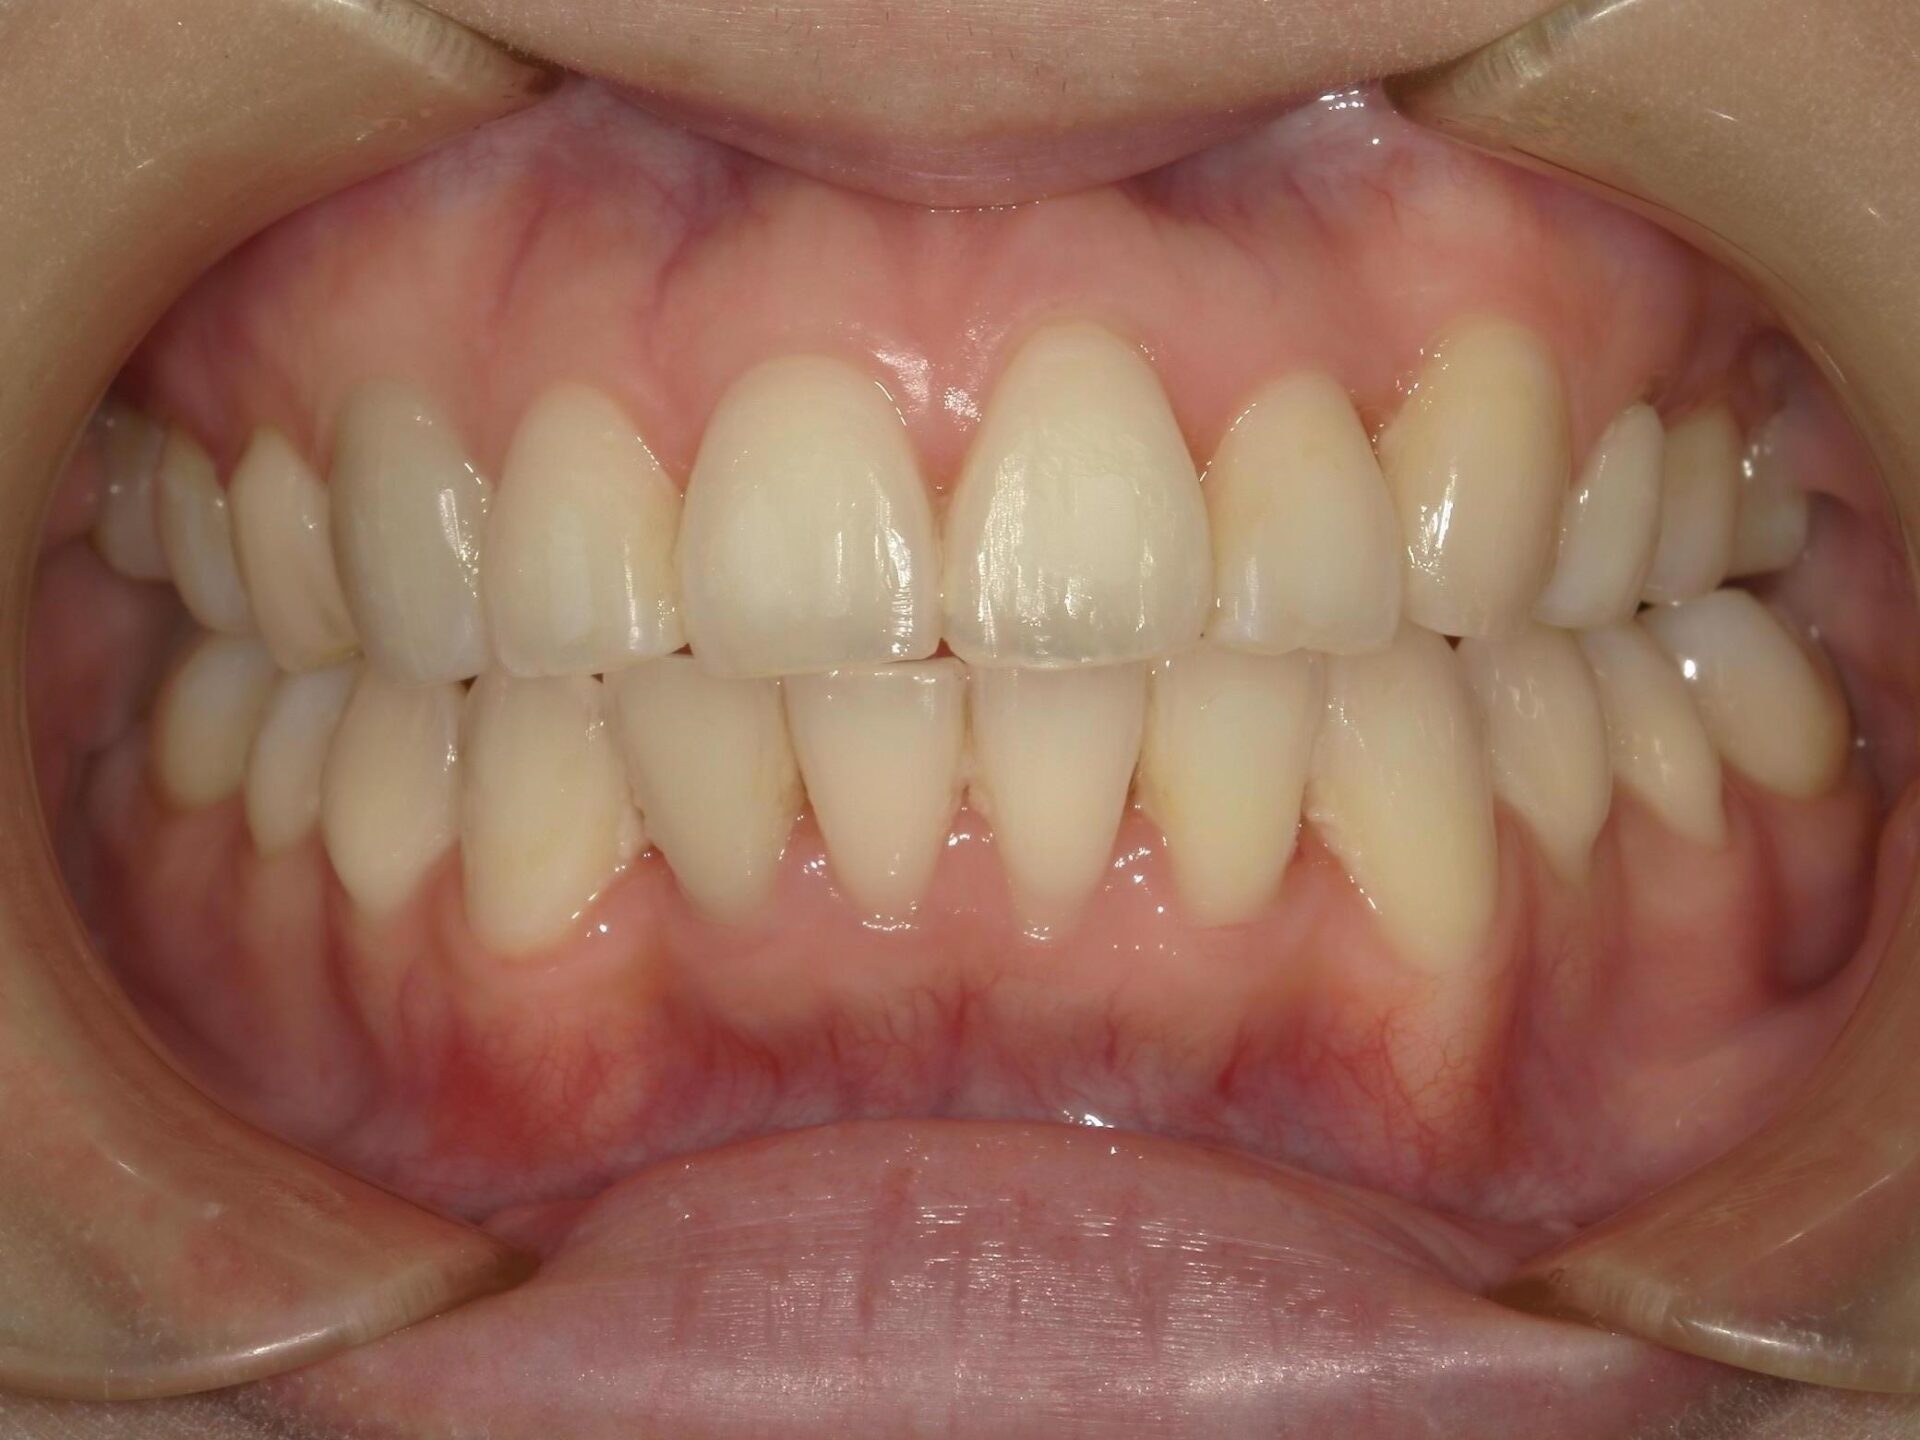

10代、女性、ワイヤー

| 施術内容 | 主訴:上下前歯でこぼこ。なるべく抜きたくない。 詳細:ワイヤー矯正での歯並び改善 詳細:ワイヤー矯正での歯並び改善 歯肉炎リスクあるため、今後は後戻りのチェックとともに歯肉炎管理もしていきます。 |

| 治療期間 | 12ヶ月(2/6現在 治療終了) |

| リスク・副作用 | ■リスク・副作用 ・治療の初期段階では、痛みや不快感が生じやすくなりますが、一週間前後で慣れます。 ・歯の動き方には個人差があるため、予想された治療期間より延長する場合があります。 |

| 費用 | ワイヤー矯正 60万円(税込660,000円) |